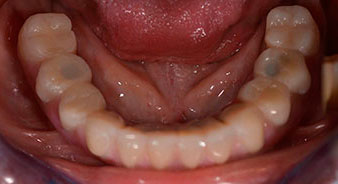

Im Anschluss erfolgt die Abformung und Bissnahme, sodass die Zahntechniker umgehend mit der Anfertigung der provisorischen Arbeit beginnen können. Diese wird im Anschluss am gleichen Tag eingeschraubt (Abb. 17 und 18).

Nach der Zeit, die für die Osseointegration benötigt wird, kann die endgültige Abformung der Implantate erfolgen und entsprechend die endgültige Arbeit angefertigt werden (Abb. 19 und 20). Hier können Behandler und Patient gemeinsam entscheiden, ob diese eine Keramik- oder Kunststoffverblendung, ein Zirkon- oder Metallgerüst bekommen soll. Im vorliegenden Fall hat sich das Team um Dr. Pascu, aufgrund der unklaren Prognose der Oberkieferbezahnung und des elongierten Zahnes 24, für eine Kunststoffverblendung entschieden. Diese ist im Allgemeinen wesentlich einfacher umzustellen und der neuen Situation im Oberkiefer anzupassen.